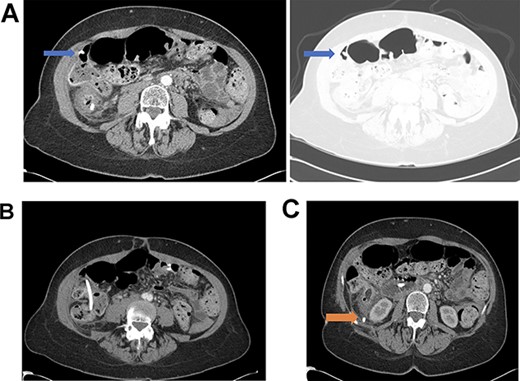

A 60-year-old female with a past medical history of metastatic gallbladder carcinoma presented to her primary oncologist with a 2-day history of abdominal pain. Her history was also significant for palliative biliary stents that had been placed 2 years ago and had been serially exchanged, most recently 2 months prior to presentation. Her oncologist obtained an outpatient abdominal computed tomography (CT) scan demonstrating the stent had caused a perforation of the right colon through the wall at the level of the hepatic flexure and perforation into the retroperitoneum at the level of the cecum without evidence of free intraabdominal air (Fig. 1A–C). The patient then presented to the emergency department for further evaluation. Upon evaluation, she was mildly tachycardic and normotensive with a temperature of 38.2°C. Physical examination was significant for mild abdominal distention and moderate tenderness to palpation in the right lower quadrant. Laboratory evaluation demonstrated a mild neutropenia but was otherwise within normal range. After extensive discussion with a multidisciplinary team including colorectal surgery, medical oncology, gastroenterology and the patient, a hybrid laparoendoscopic approach was planned to address stent removal versus a possible colectomy. The decision was made to start mechanical bowel preparation, despite possible perforation, to optimize an endoscopic attempt at retrieval, and the patient was taken to the operating room within 24 hours of presentation.

(A) Distal biliary stent perforation of the ascending colon at the level of the hepatic flexure (as indicated by arrows). (B) Stent migration at the level of the ascending colon. (C) Dislodged bile duct stent with perforation into the retroperitoneum at the level of the cecum (as indicated by arrow).